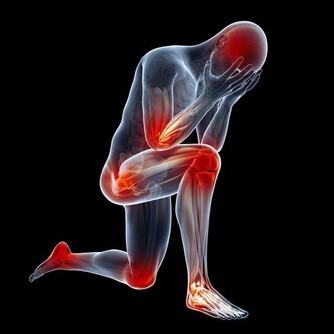

氣溫驟降時,腦血管疾病發病者明顯增加。劉霞發病時,正好遇到兩大誘因,一是天氣轉冷,二是深夜用熱水泡腳,都可能令血管受到強烈刺激,一定程度上誘發疾病。因此,有腦血管基礎性疾病的市民,近期應注意防寒保暖,避免身體遭受冷暖刺激。少用過熱的水洗澡、泡腳,少喝酒,避免情緒激動。同時,還應定時對身體進行全面檢查。

3、心臟病病人和低血壓者當心暈厥。

這類病人泡腳時要格外小心,一是水溫不可過高,二是泡腳時間不能過長,因為用熱水泡腳后,會迅速導致人體血管擴張,全身血液會由重要臟器流向體表,因此很容易使心臟、大腦等重要器官缺血缺氧,因此對於有心臟病、低血壓的人群來說,就會增加他們發病的危險。